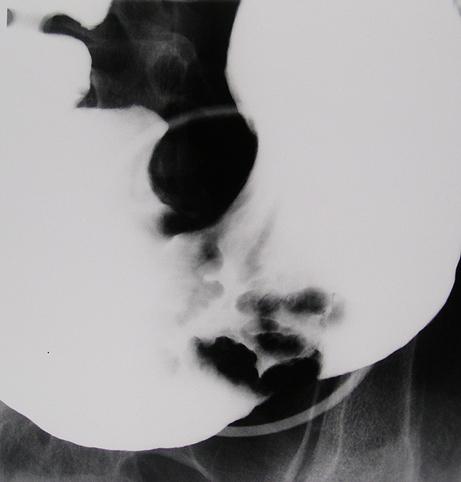

Criteria of Hist.ClassificationMalignant epithelial tumor/Adenocarcinoma

LocationStomach/More than one of above

Technique, MethodX-ray

Macroscopic TypesType 4 Diffusely infiltrating type/

Size40 -

Depth of Tumor Invasionserosa (adventitia)